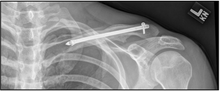

| X-ray of a left clavicle fracture | |

The basic method to check for a clavicle fracture is by an X-ray of the clavicle to determine the fracture type and extent of injury. In former times, X-rays were taken of both clavicle bones for comparison purposes. Due to the curved shape in a tilted plane X-rays are typically oriented with ~15° upwards facing tilt from the front. In more severe cases, a computerized tomography (CAT) or magnetic resonance imaging (MRI) scan is taken. However, the standard method of diagnosis through ultrasound imaging performed in the emergency room may be equally accurate in children.[1]

A discontinuity in the bone shape often results from a clavicular fracture, visible through the skin, if not treated with surgery. Surgical procedure often call for open reduction internal [plate] fixation where an anatomically shaped titanium or steel plate is affixed along the superior aspect of the bone by several screws. In some cases, the plate may be removed after healing, but this is very rarely required (based on nerve interaction or tissue aggravation), and typically considered an elective procedure. Alternatively, intramedullary fixation devices (within the medullary canal) can be implanted to support the fracture during healing. These devices are implanted within the clavicle's canal to support the bone from the inside. Typical surgical complications are infection, neurological symptoms distal the incision (sometimes to the extremity), and nonunion.